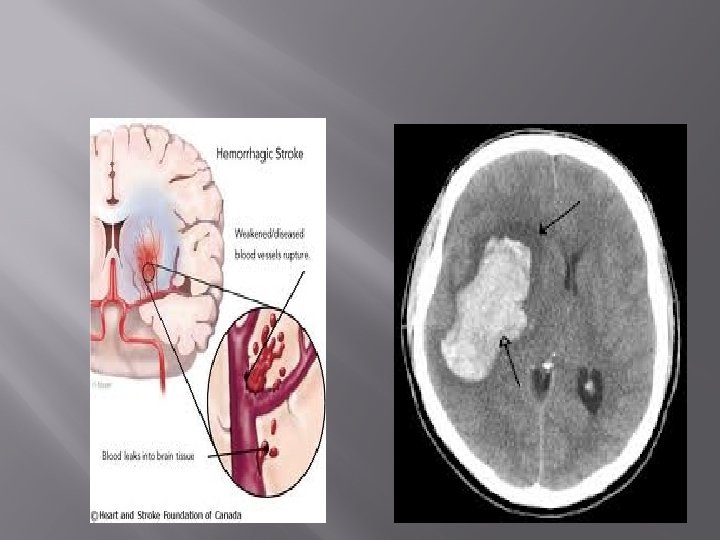

Haemorrhagic stroke � � The largest studies indicate that subarachnoid and intraceranial haemorrhage comprise 2555% of all stroke under the age of 45. The known association between hypertension and intracranial haemorrhage may explain the increased rate of intracranial haemorrhage observed among young people.

� � An important consideration in young persons presenting with intracerebral haemorrhage is the possibility of illicit drug use. Increased young haemorrhagic stroke rates were observed in association with increased rates of amphetamine and cocaine abuse over a period of three years.

conclusion � In summary, stroke in the young requires a different approach to investigation and management than stroke in the elderly given differences in the realative frequencies of underlying causes. haemorragic stroke is common , and vascular imaging is recommended given a high frequency of underlying vascular anomalies.